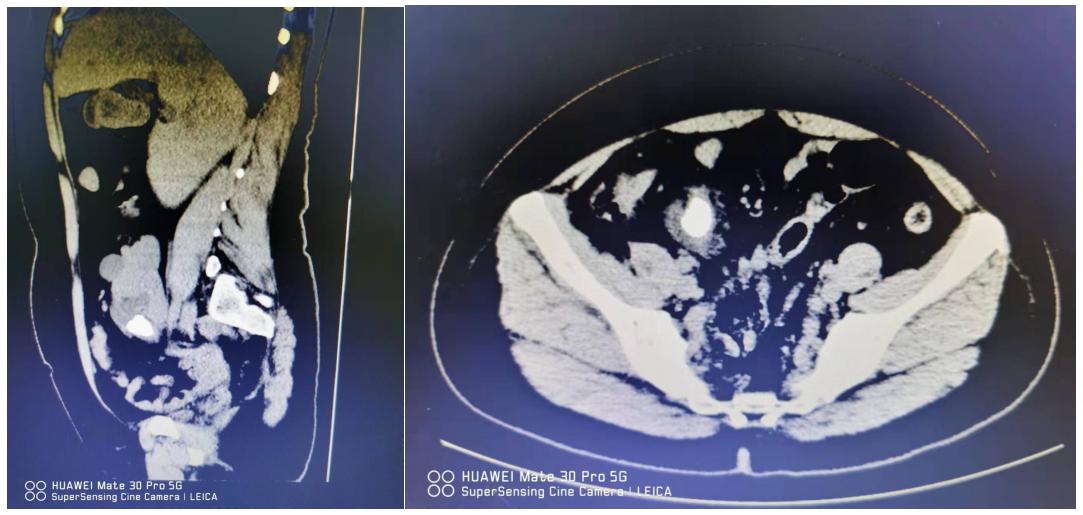

上图为患者术前三维CT重建图

“患者的彩超检查发现她的右肾出现在盆腔里,肾门朝向外前方,而正常人的肾脏位于后腰部,腹腔后方、脊柱的两侧后方。”任明华教授介绍,刘女士的右肾还有一颗直径达3cm多的结石横在肾盂内,这也是刘女士出现持续疼痛的根源。